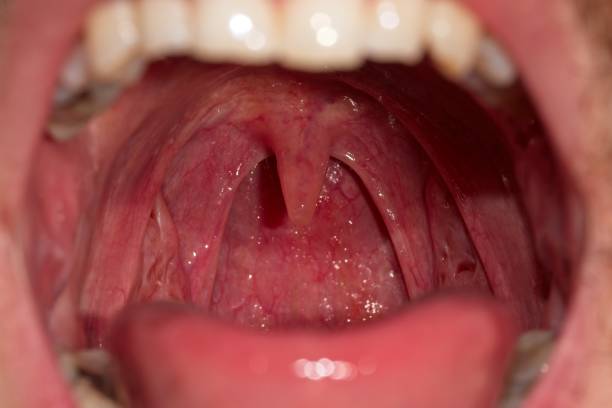

목젖 또는 구개는 입 안쪽(구개)의 처진 부분을 말합니다. 발생학적으로 입천장의 좌우 조직이 하나로 연결된 단계에 남아있는 부분입니다. 코골이는 음주나 피로로 인해 연구개나 혀 근육과 함께 종양을 일으켜 기도를 막아서 발생합니다. 또한 입천장이 큰 사람들은 코를 골기 쉽습니다.

목젖이 부었을때 증상은?

| 목젖, 목이 가려움 | 목젖이 가려워서 습관적으로 혀로 긁습니다. |

| 인후통 | 감염이 진행됨에 따라 열과 함께 인후염이 발생할 수 있습니다. |

| 목 이물감 | 이질감을 많이 느끼기 때문에 음식을 삼키기가 어렵습니다. |

| 호흡곤란 | 심한 부기는 호흡 곤란을 유발할 수 있습니다. |